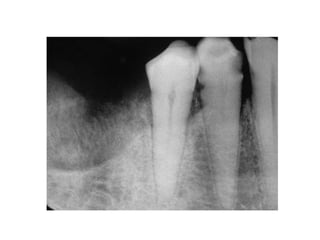

• Solitary ill

defined

radiolucent

area related to

lower right

molars and

causing

invasion of the

IAC.